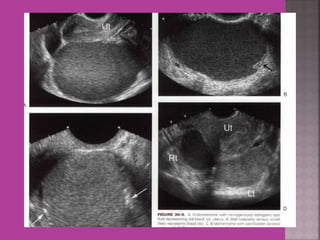

MRI-----Bilateral ovaries with PCOD changes